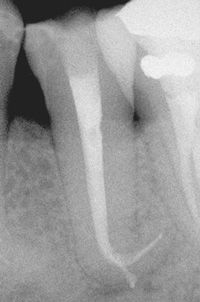

DILACERAÇÃO

Curvatura proeminente da coroa ou raiz dental

Fator Etilógico provável = Trauma durante a odontogêneses